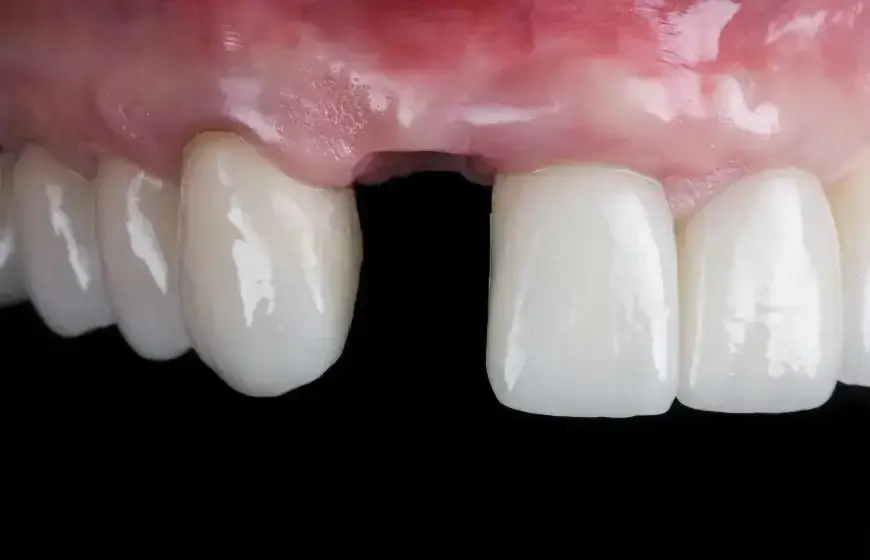

Pełna regeneracja kiedy dziąsło i kość wrócą do formy? Oś czasu od 2 tygodni do 6 miesięcy

Proces pełnej regeneracji tkanek miękkich, czyli dziąsła, oraz odbudowy kości w miejscu po usuniętym zębie jest znacznie dłuższy. Może on trwać od 3 do nawet 6 miesięcy. W niektórych przypadkach, szczególnie po skomplikowanych ekstrakcjach lub usunięciu zębów mądrości, pełna odbudowa kości, zwana osteogenezą, może zająć nawet od 6 do 12 miesięcy. Ważne jest, aby uzbroić się w cierpliwość i nadal przestrzegać zaleceń pozabiegowych, nawet gdy objawy bólu i dyskomfortu już ustąpiły.